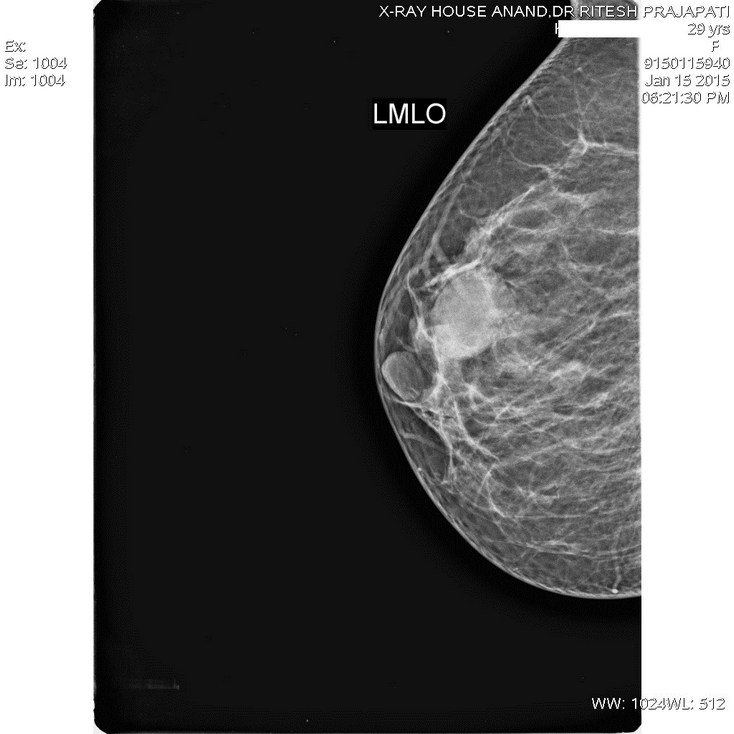

Mammography-Breast Tumor